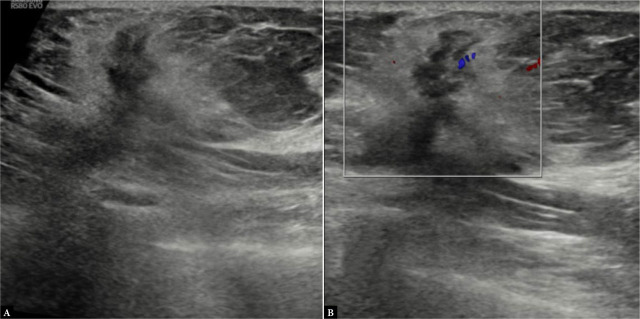

Results: A significant association between posterior acoustic features and molecular subtypes was seen. Posterior acoustic shadowing was associated with progesterone receptor status with an odds ratio (OR) of 36.58, confidence interval (CI) of 5.527-866.1, and p <0.001. The luminal type A molecular subtype was significantly higher in the posterior acoustic shadowing group (10 cases; 52.63%) with an OR of 3.85, CI of 1.12-13.98, and p of 0.02. The proportion of patients with triple-negative molecular subtype (9 cases, 50%) was significantly higher in the posterior acoustic enhancement group, with an OR of 29.42, CI of 4.117-725.4, and p <0.001. Tumors with circumscribed margins were also highly suggestive of the triple-negative molecular subtype [OR of 5.12, CI of 1.16-24.85, and p of 0.03]. The association between the presence or absence of vascularity and its type with molecular subtypes failed to show statistical significance in our study, although vascularity was more frequently observed in triple-negative molecular subtype and luminal type B Her+ve cases.

Conclusion: Certain sonographic features are associated with the estrogen/progesterone receptor hormone receptor status and molecular subtypes of breast cancer. With validation of this association, ultrasound may serve as a basic imaging modality for predicting molecular subtypes of breast cancer even in remote areas, where immunohistochemistry hormone receptor and HER2 testing are not available.